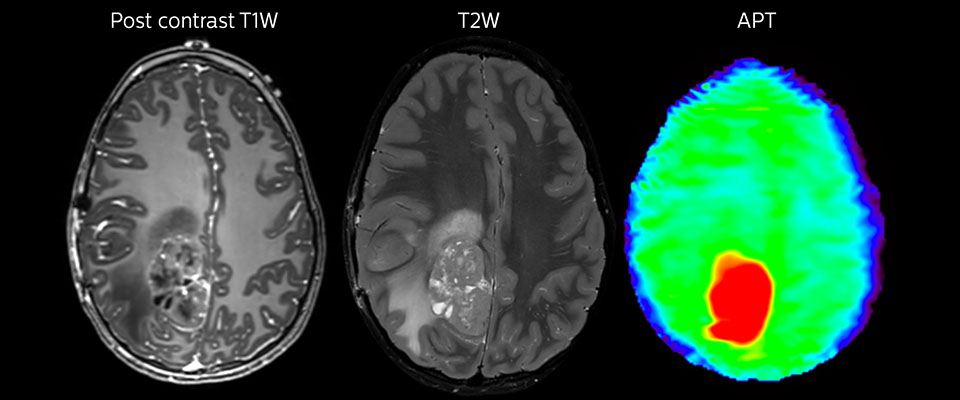

APT-Bildgebung eines hoch differenzierten Tumors

Tumorauswertung bei einem 1-jährigen Kind mit Medulloblastom. Dieser aggressive Tumortyp ist sehr solide und homogen. Das hohe APT-Signal entspricht dem kontrastverstärkten Bild dieses hoch differenzierten Tumors.